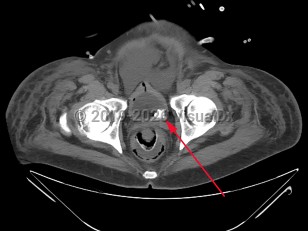

Urinary bladder calculus

Bladder stones, particularly large and nonobstructive stones, do not frequently cause symptoms. Larger stones are thought to be less able to move significantly within the bladder and cause injury to the bladder wall and seem to be less prone to lodge in the bladder infundibulum / neck and cause acute obstruction. When patients do present with symptoms, they may be nonspecific and include suprapubic discomfort, hematuria, dysuria, urinary frequency, urinary hesitancy or poor urine stream, penile pain in male patients, or cloudy urine.